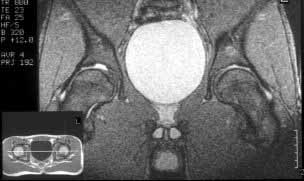

I believe this patient has anterior hip impingement caused by a retroverted acetabulum. This is seen on the submitted AP x-ray by observing the overlap of the anterior wall and posterior wall. In an acetabulum with "normal" version, the anterior wall shadow meets the posterior wall shadow at the superio- lateral aspect of the acetabulum, and they do not overlap as you follow the lines inferiorly. In an acetabulum with retroversion, the two shadows cross over the femoral head, making a figure 8 pattern.

To further confirm this, obtain a full AP pelvis film and a false profile view of both hips. In addition, the patient has an element of hip dysplasia, seen by his decreased center edge angle. On physical exam, his pain will be reproduced by hip flexion, adduction and internal rotation, when the anterior surface of the femoral neck impinges on the anterior labrum and wall. An MRI may show hypertrophic changes in the femoral neck. I also recommend a gadolinium MRI hip arthrogram to ensure there is no significant labral pathology.

Acetabular retroversion - so only it can be blamed for pain in hips? What about those holes in acetabulum - are they of no importance? T2 weighted images show them to be connected to joint cavity.

"What about those holes in acetabulum - are they of no importance? T2 weighted images show them to be connected to joint cavity."

My radiologist and I couldn't find holes in acetabulum. Perhaps you are talking about the acetabular incisura or notch. As can be seen in this image of a normal coronal hip MR from Stoller's text on MRI in Orthopaedics and Sports Medicine, the acetabular notch can have a significant extent into the weight bearing dome.